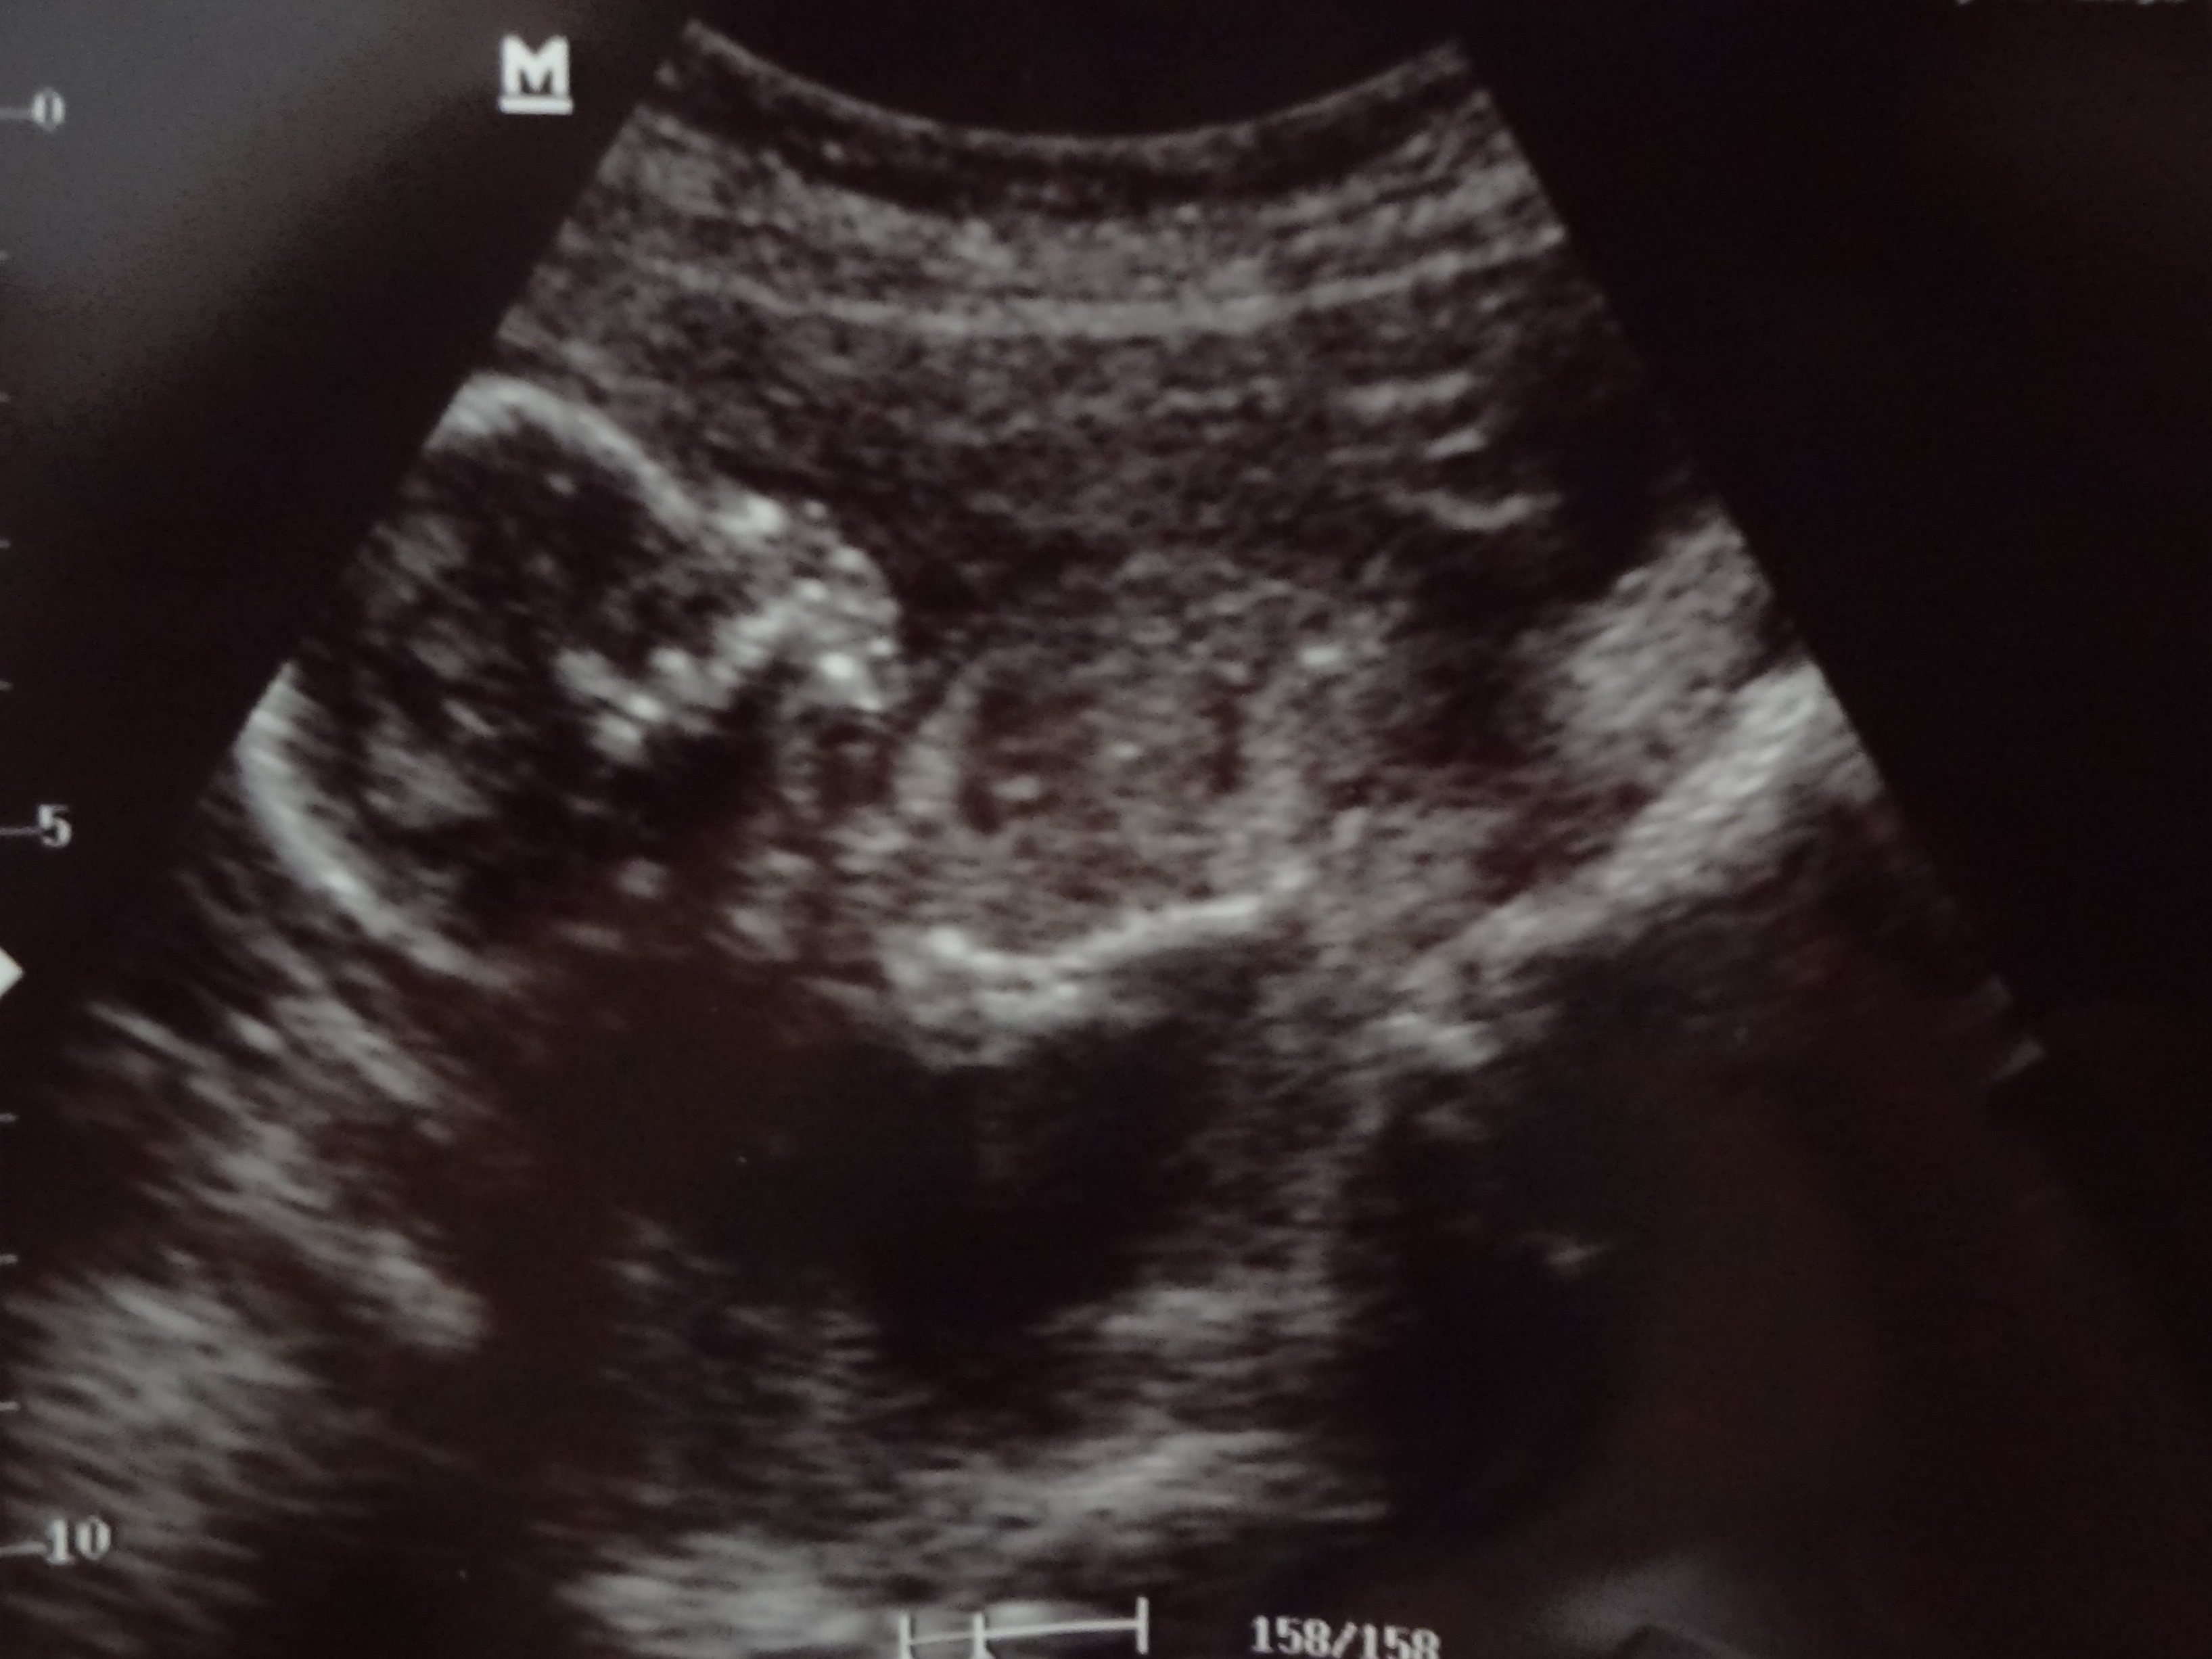

We had a doctor’s appointment today. Normally we wouldn’t find out the sex of the baby until our next appointment which is the anatomy ultrasound with the technician. However, our doctor agreed to give us a sneak peek since we were far enough along. At first the baby’s legs were crossed which the doctor thought was cute, but made me think that we weren’t getting any news today. Honestly, I had to told myself not to get my hopes up. Things might have been unclear and we could have walked out of that room with no hint. Since Baby Scott seems to be an active little one, we eventually did get a view.

We’re having a BOY!!! I thought we were having a boy from the beginning. Yes, I would have been excited if it was a girl. I get girls. I’ve built my ministry around girls and being a girl, I have a slight clue to how they are wired, but boys… Oh boys… I don’t understand them! I guess it’s time to learn! The doctor told us to keep the tags on anything blue we went out to purchase for the next month. She really wants to confirm things next time, but we all agreed that we could see the “parts” and she explained to us how she came to her conclusion. I’m fairly positive we’re having a boy. It’s hard to disagree with the photos. I won’t buy anything until after the next appointment, but at least I have some time to wrap my mind around a boy! A BOY!